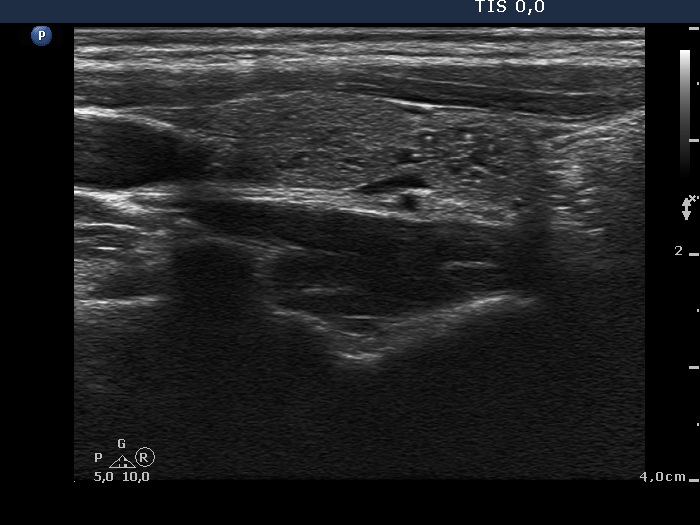

Ultrasonography: The thyroid was echonormal. There was a moderately hypoechogenic inhomogeneous nodule in the lower pole of the right lobe. There were two lymph nodes next to each other above the right thyroid in the submandibular area. The lymph nodes presented a regular hilum.

Cytology was performed from the nodule in the right thyroid and resulted in a benign colloid goiter.

It is edifying to analyze the hyperechogenic figures in the thyroid lesion. While examining the patient, I interpreted these as microcalcifications. However, by preparing the case study I had to regroup these figures. These are in fact presentations of connective tissue and colloid crystals. (See the footnotes of the relevant images.)